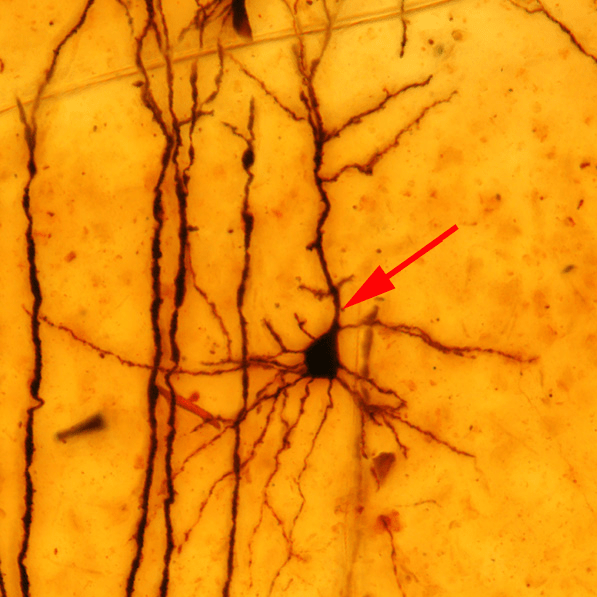

I dendriti apicali dei neuroni corticali